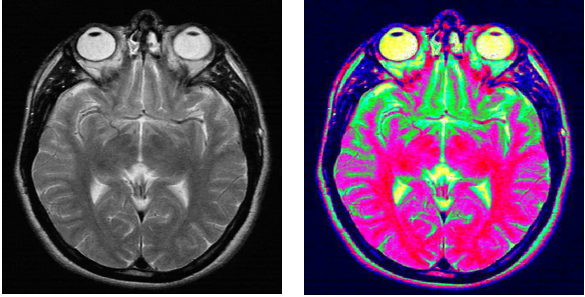

伪彩色增强就是将一幅具有不同灰度级的图像通过一定的映射转变为彩色图像,来达到增强人对图像的分辨能力。

与灰度图像相比,彩色图像除含有较大的信息量外,它的表示方式和存储结构也不相同,因此,不能将灰度图像的处理技术简单地直接应用于彩色图像。 对于无彩色(消色)图像来说,亮度(也即灰度)是唯一的属性。 亮度反映了该颜色的明亮程度。颜色中掺入的白色越多亮度就越大,掺入的黑色越多亮度就越小。 常用的彩色模型可分成两类: (2)面向诸如彩色动画图形创作等的彩色处理应用。面向彩色处理应用的模型主要是HSI模型(hue-saturation-intensity,即色调、亮度和饱和度)。 RGB彩色模型 RGB色系: HSI彩色模型 HSI(hue-saturation-intensity)彩色模型比较适合于人用色调(H)、饱和度(S)和亮度(I)描述被观察物体颜色的解释,对于开发基于彩色描述的图像处理方法是一个理想的工具。 HSI色系 —— 色度分量H H:表示色度,由角度表示。反映了该颜色最接近什么样的光谱波长。0o为红色,120o为绿色,240o为蓝色。 上图为基于圆形彩色平面的HSI彩色模型 HSI色系 —— 饱和度分量S S:表示饱和度,饱和度参数是色环的原点到彩色点的半径长度。 上图: HSI彩色模型中的色调和饱和度 RGB彩色模型到HSI彩色模型的转换 彩色变换 反色是指与某种色调互补的另一种色调。 彩色图像的灰度化 将彩色图像转变为灰度图像的处理称为彩色图像的灰度化处理。 将彩色图像转换为灰度图像的实质,就是通过对图像R、G、B分量的变换,使得每个像素点的R、G、B分量值相等。 彩色图像的灰度化方法主要包括: 人眼对绿光的亮度感觉仅次于白光,是三基色中最亮的,红光次之,蓝光最低。 真彩色转变为256色 将真彩色图像转化为256色图像会有大量的颜色信息损失掉,因此,在转换过程中要找到合适的映射关系,使得变化后的256种颜色在原图像中最具代表性或出现的频率最高。 1. 中位切分法 2. 流行色法 彩色平衡 景物中物体的颜色偏离了原来的真实色彩,原因是由于颜色通道中不同的敏感度、增光因子、偏移量等使图像的3个分量发生了不同的线性变换,导致图像的三基色“不平衡”。 常用的彩色平衡方法有: 1. 白平衡法 彩色图像增强 在得到的彩色图像中,有时会存在对比度低、颜色偏暗、局部细节不明显等问题,为了改善图像的视觉效果、突出图像的特征,利于进一步的处理,需要对图像进行增强处理。 真彩色增强的处理对象是具有 1)亮度增强 亮度增强可以在其亮度分量上使用第四章介绍的灰度图像的增强算法,如灰度变换法、直方图增强法等 2)色调增强 3)饱和度增强 伪彩色增强 伪彩色增强的处理对象是灰度图像。 伪彩色增强可分为空域增强和频域增强两种,在这两种算法中,密度分层法、灰度级-彩色变换法和频率滤波法是三种较为常用的算法。 图11.18 密度分层法空间示意图 图11.19 密度分层法平面示意图 2)灰度级-彩色变换法 灰度级-彩色变换伪彩色增强法的基本思想是:对图像中每个像素点的灰度值采用不同的变换函数进行3个独立的变换,并将结果映射为彩色图像的R、G、B分量值,由此就可以得到一幅RGB空间上的彩色图像 由于灰度级-彩色变换法在变换过程中用到了三基色原理,与密度分层法相比,该算法可有效地拓宽结果图像的颜色范围。 图11.21 灰度级-彩色变换法示意图 3)频率滤波法 首先对原灰度图像进行傅立叶变换,然后用3种不同的滤波器分别对得到的频率(谱)图像进行独立的滤波处理,处理完后再用傅立叶逆变换将得到三种不同频率的图像映射为单色图像,经过一定的后处理,最后把这三幅灰度图像分别映射为彩色图像的R、G、B分量,这样就可以得到一幅RGB空间上的彩色图像 与密度分层法和灰度级-彩色变换法两种算法相比,频率滤波法输出的伪彩色与灰度图像的灰度级无关,仅与灰度图像不同空间频率成分有关。 假彩色增强是从一幅初始的彩色图像或者从多谱图像的波段中生成增强的彩色图像的一种方法,其实质是从一幅彩色图像映射到另一幅彩色图像,由于得到的彩色图像不再能反映原图像的真实色彩,因此称为假彩色增强。 应用: 假彩色增强可以看作是一个从原图像到新图像的线性坐标变换。